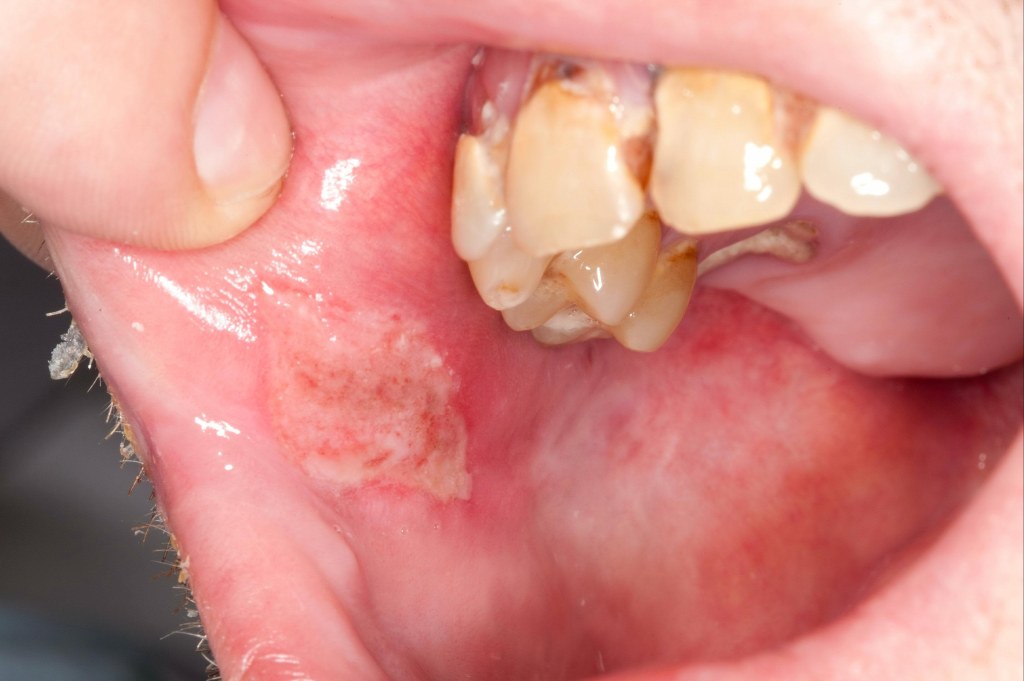

To diagnose Behcet’s Disease, the dentist and physician will first examine the patient’s oral health. He/she will look for the canker sores in the mouth and gums. The sore can be in a line on the roof of the mouth, gumline, or cheeks. This is one of the quickest and ordinary signs that may appear. Moreover, the individual will face trouble in speaking and chewing.